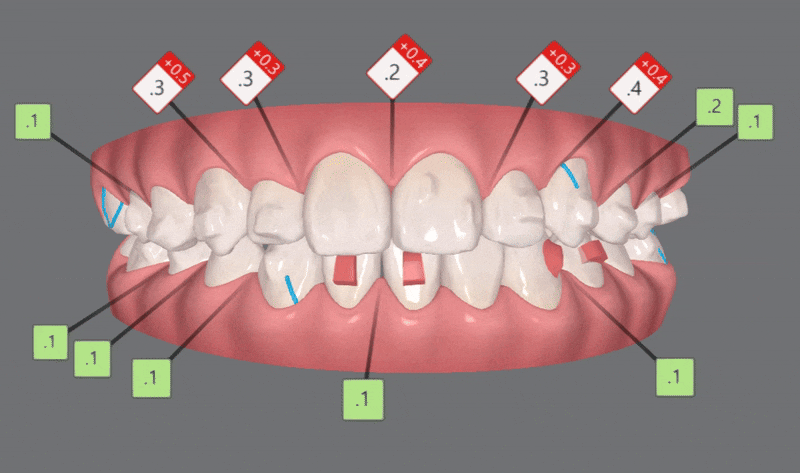

1st Clincheck(25개 장치)

교정기간: 23/8~ 24/1

25개의 장치를 통해 첫번째 클린체크를 마친후의 사진입니다

첫번째 클린체크만으로도 완성도 있게 교정이 잘 되었습니다 :)

다이아몬드등급의 치과답게

앞니의 반대교합은 3개월만에 개선이 되었다는 사실!!